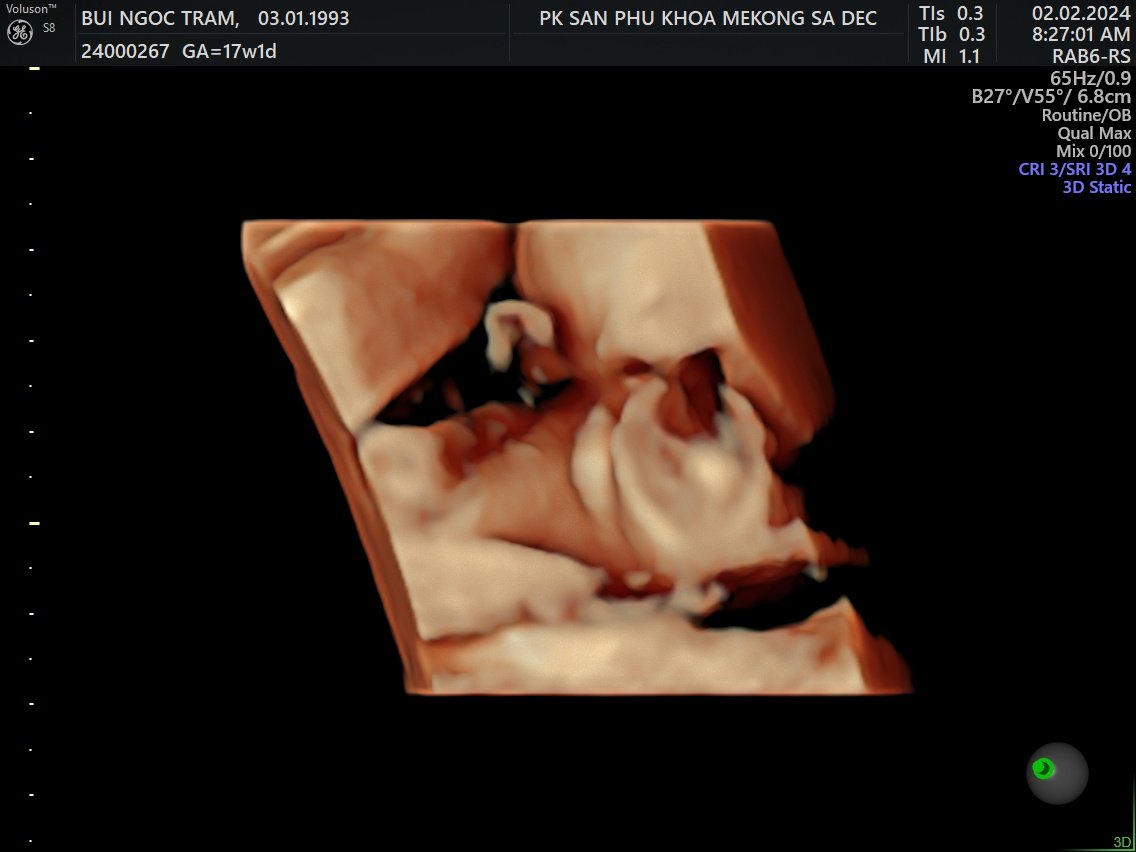

Siêu âm 5D

Tuần 17

2 Feb 2024

Về Sadec, được đi siêu âm 5DLà con trai, hơi ú và hành mẹ bị viêm bạch huyết, hên là phát hiện sớm và được bác sĩ cho thuốc!